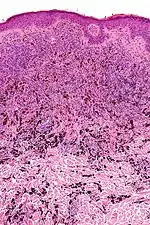

| Micrograph of a blue nevus showing the characteristic pigmented melanocytes between bundles of collagen. H&E stain. | |

Blue nevus